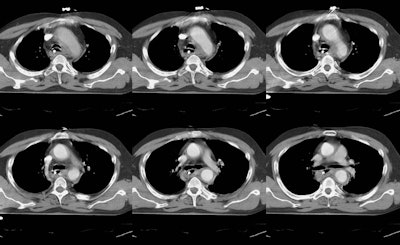

The chest CT and arteriogram on this patient are shown below. The CT demonstrates the presence of standy increased density within the mediastinal fat suggesting a mediastinal hematoma. There is also a focal change in the aortic caliber near the isthmus, and an intralumenal flap can be seen at this level (last image on top row, and first image on bottom row). Despite the CT findings, an arteriogram was performed which again demonstrated the post-traumatic aortic pseudoaneurysm.